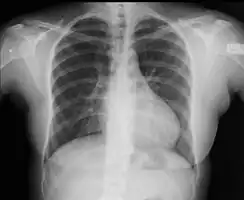

With imaging, resorption of the lower part of the ribs may be seen, due to increased blood flow over the neurovascular bundle that runs there. Prestenotic dilatation of the aortic arch and left subclavian artery, as well as indentation at the site of coarctation results in a classic 'figure 3 sign' on x-ray. The characteristic bulging of the sign is caused by dilatation of the aorta due to an indrawing of the aortic wall at the site of cervical rib obstruction, with consequent poststenotic dilatation. This physiology results in the '3' image for which the sign is named.[5][6][7] When the esophagus is filled with barium, a reverse 3 or E sign is often seen and represents a mirror image of the areas of prestenotic and poststenotic dilatation.[8]

Aortic coarctation using different imaging techniques[10] -

Coarctation of the aorta -

Coarctation of the aorta